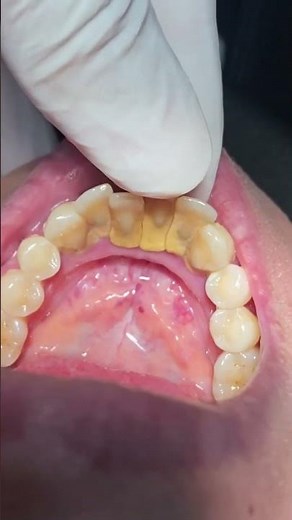

Grade III of Tooth Mobility #loosetooth #tooth #mobility

Types of Tooth Mobility... #Grade 1 #Grade 2 #Grade 3

Mobility Test

Tooth Mobility..

Tooth mobility